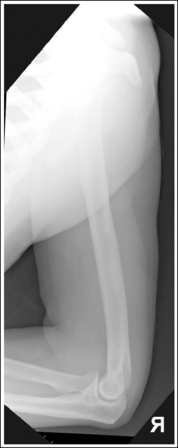

See Figures 4-86 and 4-87 and Box 4-22.

The humerus is in an AP projection. The medial and lateral humeral epicondyles are demonstrated in profile, and the radial head and tuberosity are superimposed over the lateral aspect of the proximal ulna by approximately 0.25 inch (0.6 cm). The greater tubercle is demonstrated in profile laterally, the humeral head is demonstrated medially in profile, and the vertical cortical margin of the lesser tubercle is visible approximately halfway between the greater tubercle and the humeral head.

• An AP projection is obtained by placing the patient in a supine or upright AP projection, with the affected arm extended. Supinate the hand and externally rotate the elbow until an imaginary line drawn between the palpable humeral epicondyles is aligned parallel with the IR (Figure 4-88). This positioning places the proximal radius anterior to the ulna, causing the radial head and tuberosity to be superimposed over the lateral ulna by approximately 0.25 inch (0.6 cm), and places the greater tuberosity in profile.